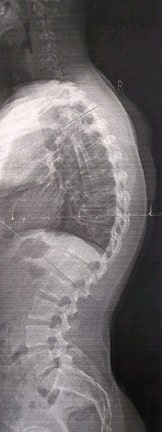

Dort wurde das erste Mal wirklich alles richtig Vermessen und es kam heraus, dass ich thorakale Hyperkyphose von 70° habe und einen kleinen Bandscheibenvorfall auf der Höhe Th4/5 ohne Rückenmarkkompression.

So sah meine Wirbelsäule Anfang 2018 aus: 2018 habe ich mich hier dann auch angemeldet, ein bisschen gestöbert und mir daraufhin eingeredet, dass es bei mir nicht so schlimm sein wird und leider an meinem bisherigen Konzept festgehalten, dass mir hin und wieder Phasen ermöglicht hat, in denen meine Verspannung nur geringfügig da waren.